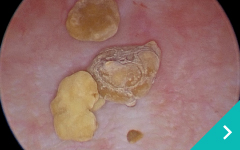

レーザー結石破砕

レーザー

結石破砕